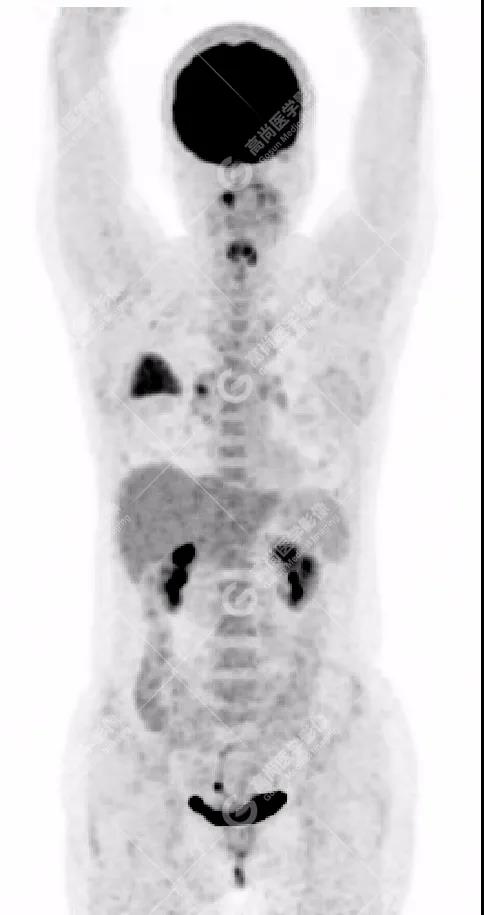

PET/CT影像圖

右肺上葉斑片狀高密度影,部分實變,邊界清楚,未跨葉間裂;內(nèi)空氣支氣管征、蟲蝕樣空洞、周圍暈征;放射性攝取增高,SUVmax=4.1。